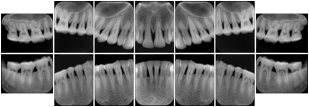

Intra-oral radiography typically involves acquisition of multiple images of various parts of the dentition. Many digital radiographic systems offer customized templates that are used for displaying the images in a study on the screen. These templates may also be referred to as mounts or view sets. The Structured Display Object represents a standard method of encoding and exchanging the layout and intended display of Structured Displays. A structured display object created in this manner could be stored with a study and exchanged with images to allow for complete reproduction of the original exam.

In most standard cases, images are oriented in structured layouts. These structured displays are useful to be shared between providers for reference purposes.

Table OO.1.1-1 shows structured display standard templates, where Viewset ID is based on the Japanese Society for Oral and Maxillofacial Radiology (JSOMR) classification provided by JIRA (Japan Medical Imaging and Radiological Systems Industries Association, www.jira-net.or.jp). Expected or typical teeth to be imaged location, region and designation codes are based on ISO 3950-2010, Dentistry - Designation system for teeth and areas of the oral cavity. For all the hanging protocols listed in OO.1.1-1, the value to use for Hanging Protocol Creator (0072,0008) is "JSOMR" and the value to use for Hanging Protocol Name (0072,0002) does not include "JSOMR" (e.g., "DL-S001A", not "JSOMR DL-S001A").